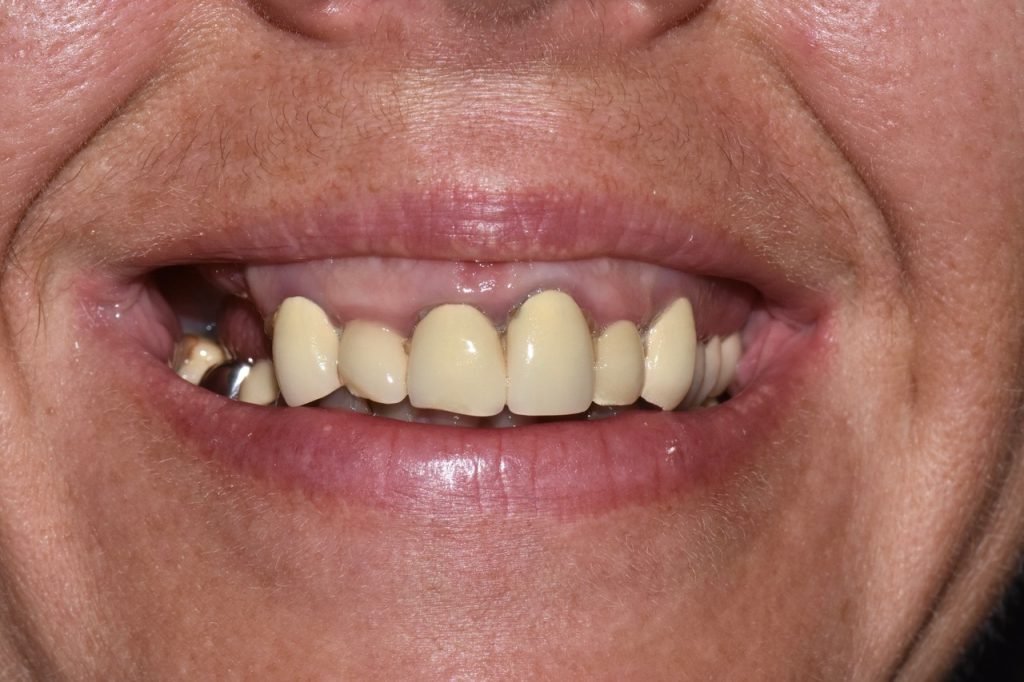

Les implants visent à remplacer une ou plusieurs dents absentes

Si l’ensemble des dents doit être remplacé par des implants, nous pouvons réaliser des traitements de l’arcade complète appelés « all on 4 » ou « all on 6 » ; ceci permet de remplacer l’ensemble des dents d’une arcade avec 4 ou 6 implants si la situation le permet.